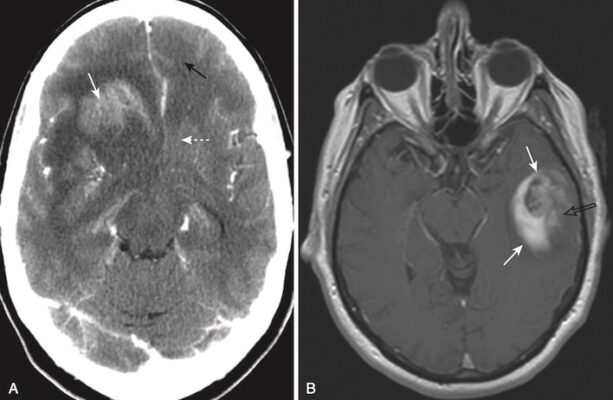

- Các khối trong não đơn độc được chia đều giữa di căn đơn độc và u não nguyên phát. Khoảng 40% của tất cả các khối u nội sọ là di căn. Các ung thư nguyên phát thường gặp di căn đến não là các khối u ác tính ở phổi, vú và u hắc tố (melanoma).

- Nhận biết di căn đến não:

- Di căn đến não thường các khối tròn, bờ xác định rõ gần chỗ nối chất xám – chất trắng.

- Thường là nhiều khối nhưng có thể đơn độc một khối.

- Chúng thường là giảm tín hiệu hoặc đồng tín hiệu trên CT không cản quang.

- Với thuốc cản quang tĩnh mạch, chúng có thể tăng cường tín hiệu, đôi khi có tăng tín hiệu dạng vòng nhẫn (ring enhancement).

- Hầu hết gây phù nề do mạch máu, thường không tương xứng với kích thước của khối u (Hình 28).